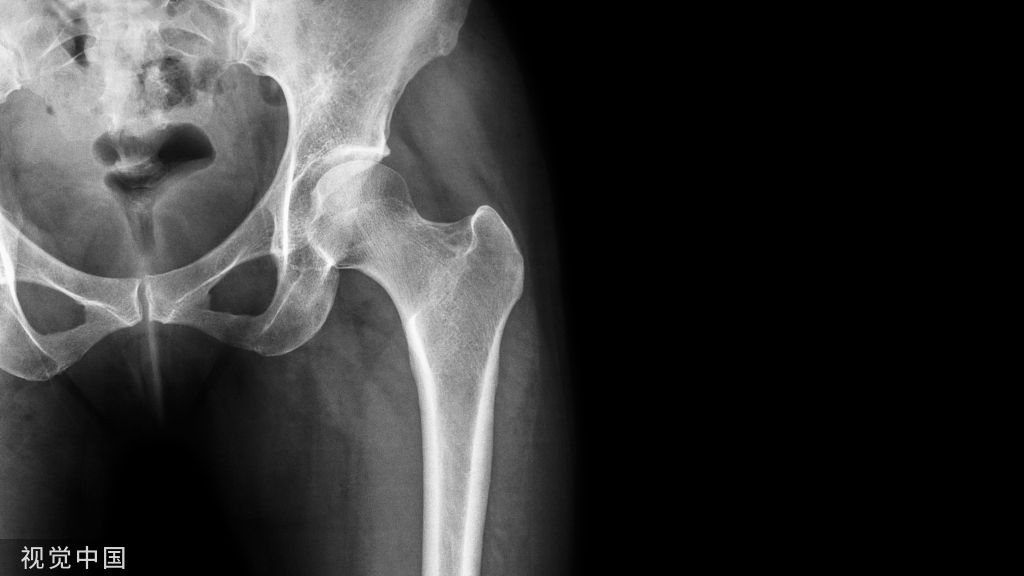

(二十三)右髋关节置换术

1.患者麻醉成功后,取左侧卧位,常规碘酒、酒精消毒术区皮肤,铺无菌单。

2.取后外侧切口,以大粗隆为中点,近端在髂后上棘与粗隆连线外三分之一,远端在大腿远侧,长约15厘米。切开皮肤及皮下组织,浅筋膜、深筋膜,显露外旋肌在大粗隆的止点,将该肌在止点处切断,向近端翻起,显露后关节囊。

3.T子型切开后关节囊,吸取关节腔积液,可见右股骨头已变形,周围有增生骨赘。电锯距离小粗隆1厘米处垂直股骨颈阶段股骨颈,取出股骨头,测量直径,选合适的假体,直径在46mm。

4.处理髋臼,将髋臼边缘增生的组织切除,将臼底滑膜及圆韧带切除。以球形磨钻打磨髋臼至软骨面完全去除。冲洗后擦干,置入骨水泥,安装46mm髋臼假体。

5.股骨安装假体,开口器开髓,髓腔挫扩髓,打入试模假体,安装试模,内旋内收,屈膝屈髋,复位,各方向活动无脱位现象。

6.脱位,取出试模假体,脉冲冲洗髓腔干净。调骨水泥,放入栓子,打入骨水泥,安装假体,安装满意后再次复位髋关节,各方向活动,无脱位表现。

7.冲洗、止血,缝合外旋肌,放置引流管,缝合深筋膜,皮下组织、皮肤。手术进行顺利,患者送恢复室并安返病房,术后外展外旋位平卧。